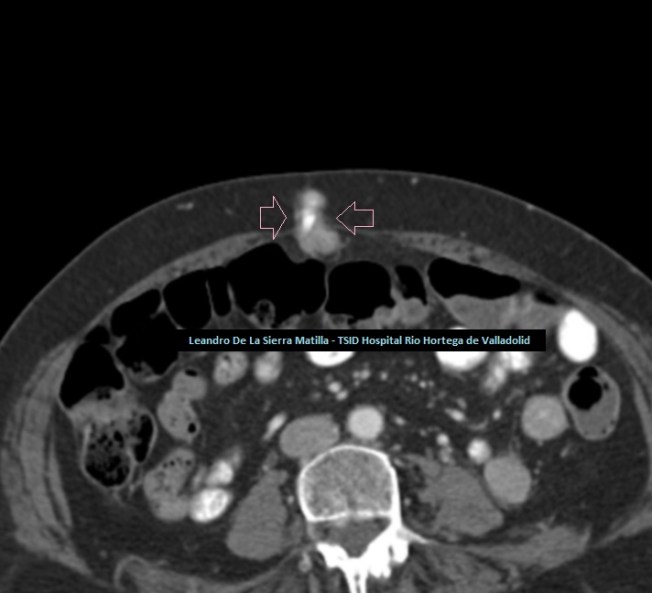

Se realiza Tc con contraste para completar estudio de extensión, en el que se confirman los hallazgos visualizados en la ecografía incluido el nódulo metastásico umbilical (FIGURA 8).

8